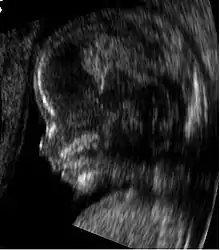

Embryon à 8 semaines

L'embryon mesure entre 15 et 22 mm. La vésicule vitelline qui le nourrit est juste à côté. À la fin de cette semaine, les coudes deviennent visibles

Fœtus à 9 semaines

L'embryon s'appelle désormais fœtus. À cet âge, la fréquence cardiaque du fœtus atteint son maximum à 175 battements par minute.